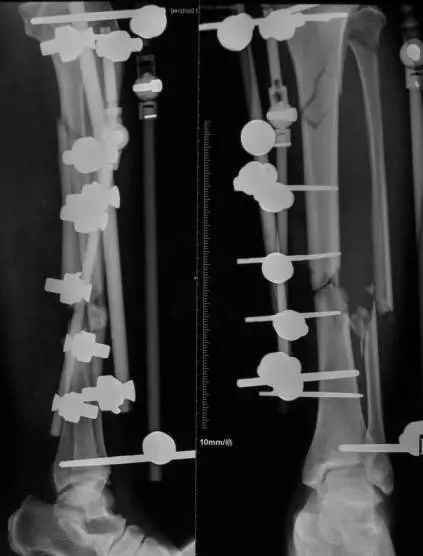

(网友提供)最后的病例是伤后40天由外地转来。开放骨折外固定架固定,骨坏死外露,用连珠和双氧水冲洗。入院时还存在足下垂,腓神经损伤、胫后动脉损伤。

Tips

• 接收该患者后第一次手术  清除病灶去除死骨27cm

• 抗生素骨水泥填塞。远端整块水泥包裹外露骨质,近端连珠以便骨搬移

• 钢丝克氏针张力牵拉皮肤,缩小创面

• 5天后下地部分负重走路

• 联合骨牵引纠正足下垂,5天后足下垂纠正后去除跟骨骨牵引针,保留胫跖骨牵引维持足于功能位。

• 而后行骨搬移、半开放植骨(如下)

• 第一次的骨水泥于80天后去除,行半开放植骨(植骨表面覆盖抗生素骨水泥)

• 因为有皮肤缺损,用骨水泥做成瓦片闭合伤口=半开放植骨

• 自体优质松质骨(如图)

• 皮肤采用了钢丝牵张闭合

• 骨搬移+半开放植骨=治疗缺损

• 植骨后一个月去除瓦片骨水泥,创面新鲜

• 钢丝克氏针张力闭合伤口加游离植皮

• 继续骨搬移

• 修整

• 入院6个月腓总神经恢复,胫前动脉再通

• 总的治疗过程2年基本完全康复